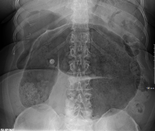

An x-ray of a person with a small bowel volvulus.